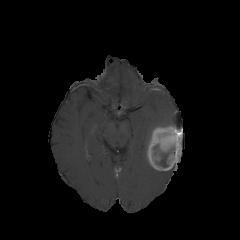

We first introduce a method for connecting the output of a CNN to an ACM, yielding a model for the precise delineation of lesions, to which we refer as Deep Active Lesion Segmentation (DALS) (Figure 4). We then go further to introduce a truly unified framework (Figure 5) that bridges the gap between ACMs and CNNs by leveraging a novel, automatically differentiable level-set ACM with trainable parameters that allows for back-propagation of gradients and can be end-to-end trained along with a backbone CNN from scratch, without any CNN pre-training. The ACM is initialized directly by the CNN and utilizes an energy functional that is locally-tunable by the backbone CNN, through 2D feature maps. Thus, our work overcomes the big hurdle of fully automating the powerful ACM approach to image segmentation. We have applied our proposed framework to the task of building segmentation in aerial images (Figure 6).

Deep Active Lesion Segmentation

[45]: Lesion segmentation is an important problem in computer-assisted diagnosis that remains challenging due to the prevalence of low contrast, irregular boundaries that are unamenable to shape priors. We introduce Deep Active Lesion Segmentation (DALS), a fully automated segmentation framework that leverages the powerful nonlinear feature extraction abilities of FCNs and the precise boundary delineation abilities of ACMs. Our DALS framework benefits from an improved level-set ACM formulation with a per-pixel-parameterized energy functional and a novel multiscale encoder-decoder CNN that learns an initialization probability map along with parameter maps for the ACM. We evaluate our lesion segmentation model on a new Multiorgan Lesion Segmentation (MLS) dataset that contains images of various organs, including brain, liver, and lung, across different imaging modalities—MR and CT. Our results demonstrate favorable performance compared to competing methods, especially for small training datasets. -